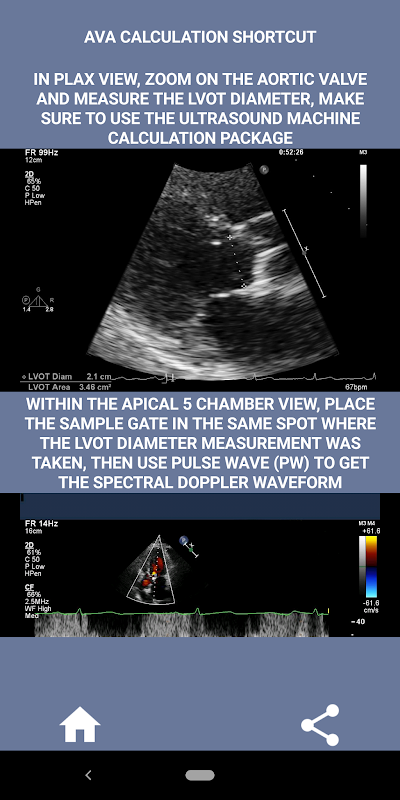

Naar mijn mening, als een geïnterviewde deze vaardigheid sterk kan demonstreren, heeft die persoon een enorm voordeel ten opzichte van de andere kandidaten die zwak zijn op dit gebied (dat is gewoon logisch omdat er normaal zoveel gevallen van aortastenose zijn). Als je solliciteert naar een functie als hartsonograaf, iemand die gewoon zijn vaardigheden moet opfrissen, of een echostudent, dan is deze app met jou in gedachten ontworpen door een momenteel praktiserende hartsonograaf. Eenvoudig en kort, direct ter zake met veel illustratieve video's die precies aangeven waar te meten (bijv. LVOT-diameter) en hoe te meten volgens de gepubliceerde ASE/ICAEL-richtlijnen.